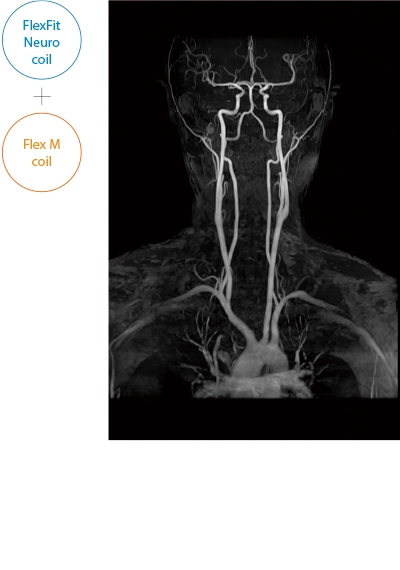

After the completion of MRA imaging, it automatically performs clipping for cerebral MRA. The automatic clipping identifies the extraction range based on the characteristics of the head. Additional clipping can also be performed on the images after the automatic clipping process.

The ECHELON Synergy ZeroHelium is equipped with a flexible head and neck coil that allows one-action setup via sliding installation, as well as a Flex coil that provides wide and flexible coverage of the imaging area. This enables flexible adaptation to different part of body.